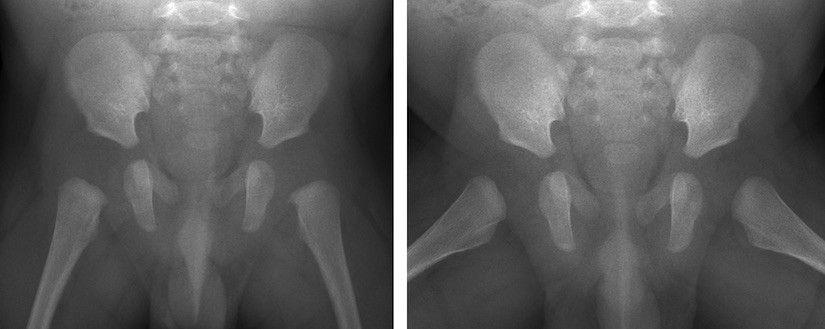

Links: voorachterwaartse röntgenfoto (AP-opname) met de benen gestrekt van het bekken van een baby van 3 maanden.

Rechts: voorachterwaartse röntgenfoto in kikkerhouding (Lauensteinopname) van het bekken van een baby van 3 maanden.

Links: voorachterwaartse röntgenfoto (AP-opname) met gestrekte benen van het bekken van een kind van 12 maanden.

Rechts: voorachterwaartse röntgenfoto in kikkerhouding (Lauensteinopname) van het bekken van een kind van 12 maanden.

Om de heup goed in beeld te brengen, wordt meestal een foto in twee richtingen gemaakt. Als je in één richting fotografeert, kan iets belangrijks wegvallen. Vaak wordt het hele bekken gefotografeerd om beide heupen met elkaar te kunnen vergelijken.

Bij kinderen wordt meestal een bekkenfoto van voor naar achter gemaakt (AP-opname: anterior posterior) met de benen gestrekt. De tweede foto wordt dan gemaakt met de benen in de zogenaamde kikkerpositie. Dit heet een Lauensteinopname. Hiermee kan onder andere worden gekeken of de heupkop goed in de kom staat en kan de vorm van de heupkop in twee richtingen worden gecontroleerd.